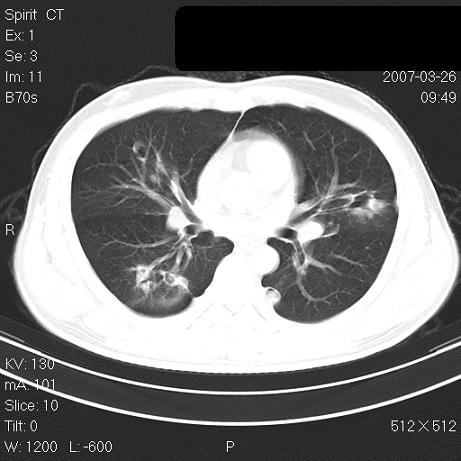

标题: CT7171B:补充治疗后2周复查 [打印本页]

标题: CT7171B:补充治疗后2周复查

治疗后2周复查,请讨论

结合以前的ct片,还是考虑肺挫伤,吸收多了。

支持:创伤性湿肺。现肺挫裂伤(出血 积气)大部分吸收。建议继续治疗!

结合以前的ct片,支持创伤性湿肺。现大部分吸收。

支持:创伤性湿肺、肺挫裂伤。现肺挫裂伤(出血、渗出、液气腔)大部分吸收。建议继续治疗!

支持:创伤性湿肺、肺挫裂伤。现肺挫裂伤(出血、渗出、液气腔)大部分吸收.

经治疗后病灶明显吸收,考虑创伤性湿肺、肺挫裂伤